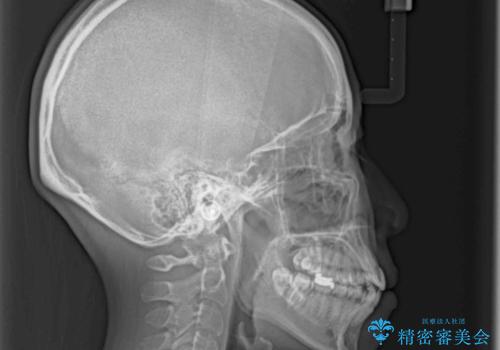

- 上下の八重歯を気にして来院された患者様です。

八重歯の後ろの歯を1歯抜歯し、補助装置(リンガルアーチ)を用いて八重歯の位置を改善し、その後インビザラインにより矯正治療を行うこととしました。

右側のみ上下小臼歯を抜歯したため、上下の正中が右にずれてしまう可能性があります。

また、元々右側は上下が咬み合っていないため、矯正をしても咬み合わないことも考えられました。

治療期間はかかりましたが、正中も合い、綺麗な仕上がりとなりました。